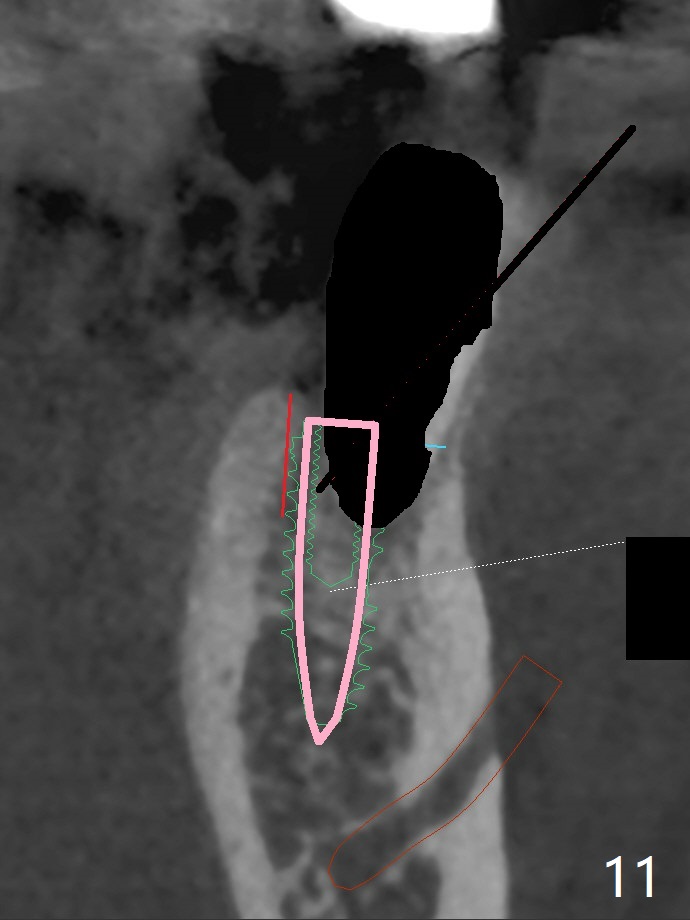

Re-analysis of preop CT reveals extensive bone loss around #18 (Fig.1 (lingual view)). Blood is withdrawn for sticky bone. After implant placement (Fig.2), sticky bone is placed at #18 (Fig.3 red dashed line (yellow: superior border of the Inferior Alveolar Canal)). PRF membrane and an immediate provisional FPD (#18-20) further keep the bone graft in place for healing. Four months postop, the patient reports difficulty in mastication on the left and requests extraction of the tooth #20 for implant (Fig.4). The implant will be placed lingually, while socket shield will be performed buccally (Fig.5 S) to keep bone graft in place. The implant at #19 is equicrestal (Fig.6); the one at #18 is apparently supracrestal buccally (Fig.7). Since there is a lot of scattering from nearby crowns, the implant at #20 will be placed free hand. To overcome the thick dense lingual plate (Fig.8 L), osteotomy is initiated (Fig.9 red line) in the middle of the lingual wall of the extraction socket (black area) on the top of the socket shield (S). After the last drill (3.5x11.5 mm, Fig.10 pink) and before 4x11.5 mm implant, use Lindamann bur to remove the coronal portion of the lingual plate (Fig.11 red line) to prevent implant buccal deviation.